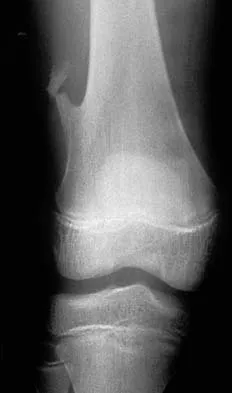

Figures 7a and 7b show the radiographs of a 51-year-old woman who injured her left leg after falling off a stepladder. Surgical reconstruction is performed with a compression screw and side plate; the postoperative radiograph is shown in Figure 7c. Following gradual progression of weight bearing, she reports that she slipped again and placed full weight on the extremity. She now notes a new onset of increased pain in her left thigh and hip region. Follow-up radiographs are shown in Figures 7d and 7e. Reconstruction should consist of

The initial fracture was an unstable reverse oblique intertrochanteric fracture with subtrochanteric extension. Initial fixation with a high-angled screw and side plate construct may not provide stability as well as a 95 degree fixed-angle device or a intramedullary hip screw device. The follow-up radiographs show loss of fixation and further propagation of the fracture distally. Reconstruction would best be accomplished with hardware removal and conversion to a long intramedullary nail with femoral head fixation or a 95 degree angled plate and screw device. Conversion to a longer plate does not improve the biomechanical situation at the primary fracture site. In situ bone grafting would not provide any additional stability and would not correct the deformity. The proximal femoral fracture is not amenable to retrograde nailing. Cerclage wiring will not sufficiently enhance stability and is not indicated. Bridle SH, Patel AD, Bircher M, Calvert PT: Fixation of intertrochanteric fractures of the femur: A randomized prospective comparison of a gamma nail and dynamic hip screw. J Bone Joint Surg Br 1991;73:330-334. DeLee JC: Fractures and dislocations of the hip, in Rockwood CA Jr, Green DP, Bucholz RW, Heckman JD (eds): Rockwood and Green's Fractures in Adults, ed 4. Philadelphia, PA, Lippincott-Raven, 1996, pp 1659-1825. Haidukewych GJ, Israel TA, Berry DJ: Reverse obliquity fractures of the intertrochanteric region of the femur. J Bone Joint Surg Am 2001;83:643-650.